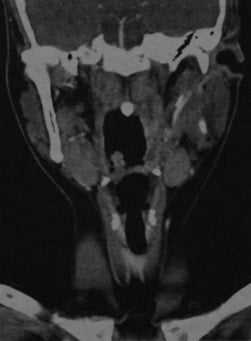

КТ с контрастированием: левосторонний паратонзиллярный абсцесс. Образование имеет гипоинтенсивный центр, окруженный усиленной стенкой. Отек левой нёбной миндалины и слизистой глотки на стороне поражения вызывает асимметричное сужение глотки. Рот остается открытым в связи с болевым синдромом.

КТ с контрастированием (реконструкция во фронтальной плоскости): левосторонний паратонзиллярный абсцесс. Выявляется перифокальный отек и повышенная плотность слизистой, а также асимметричное сужение ротоглотки, распространяющееся в дистальном направлении слева от мягкого нёба. В абсцессе наблюдается типичное периферическое усиление с гипоинтенсивной полостью в центре.